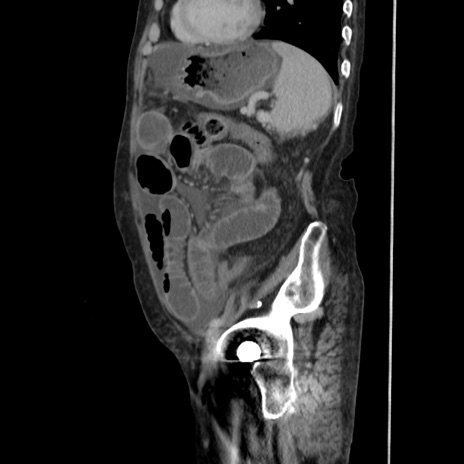

症例31(矢状断像)

【症例】80歳代 女性

【主訴】腹部膨満感

【現病歴】他院にて肝硬変にてフォロー中。1週間前から便秘、腹部膨満感、臍部腫瘤あり受診となる。

【既往歴】肝硬変

【身体所見】腹部膨隆あり、皮膚変化なし、疼痛なし。

【データ】WBC 4600、CRP 0.25

横断像